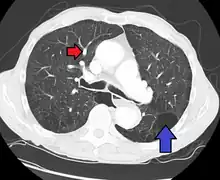

CT scan

Pulmonary artery hypertension and emphysema as seen on a CT scan with contrast

Signs of pulmonary hypertension on CT scan of the chest are:

• Increased ratio of the diameter of the main pulmonary artery (pulmonary trunk) to the ascending aorta (measured at its bifurcation).

• A ratio of 1.0 is suggested as a cutoff in adults.[59]

• Cutoff ~1.09 in children.[59]

• Increased diameter ratio of segmental arteries to bronchi. This finding in three or four lobes, in the presence of a dilated pulmonary trunk (≥29 mm), and absence of significant structural lung disease confers a specificity of 100% for pulmonary hypertension.[59]

• Mural calcification in central pulmonary arteries is most frequently seen in patients with Eisenmenger's syndrome.[59]